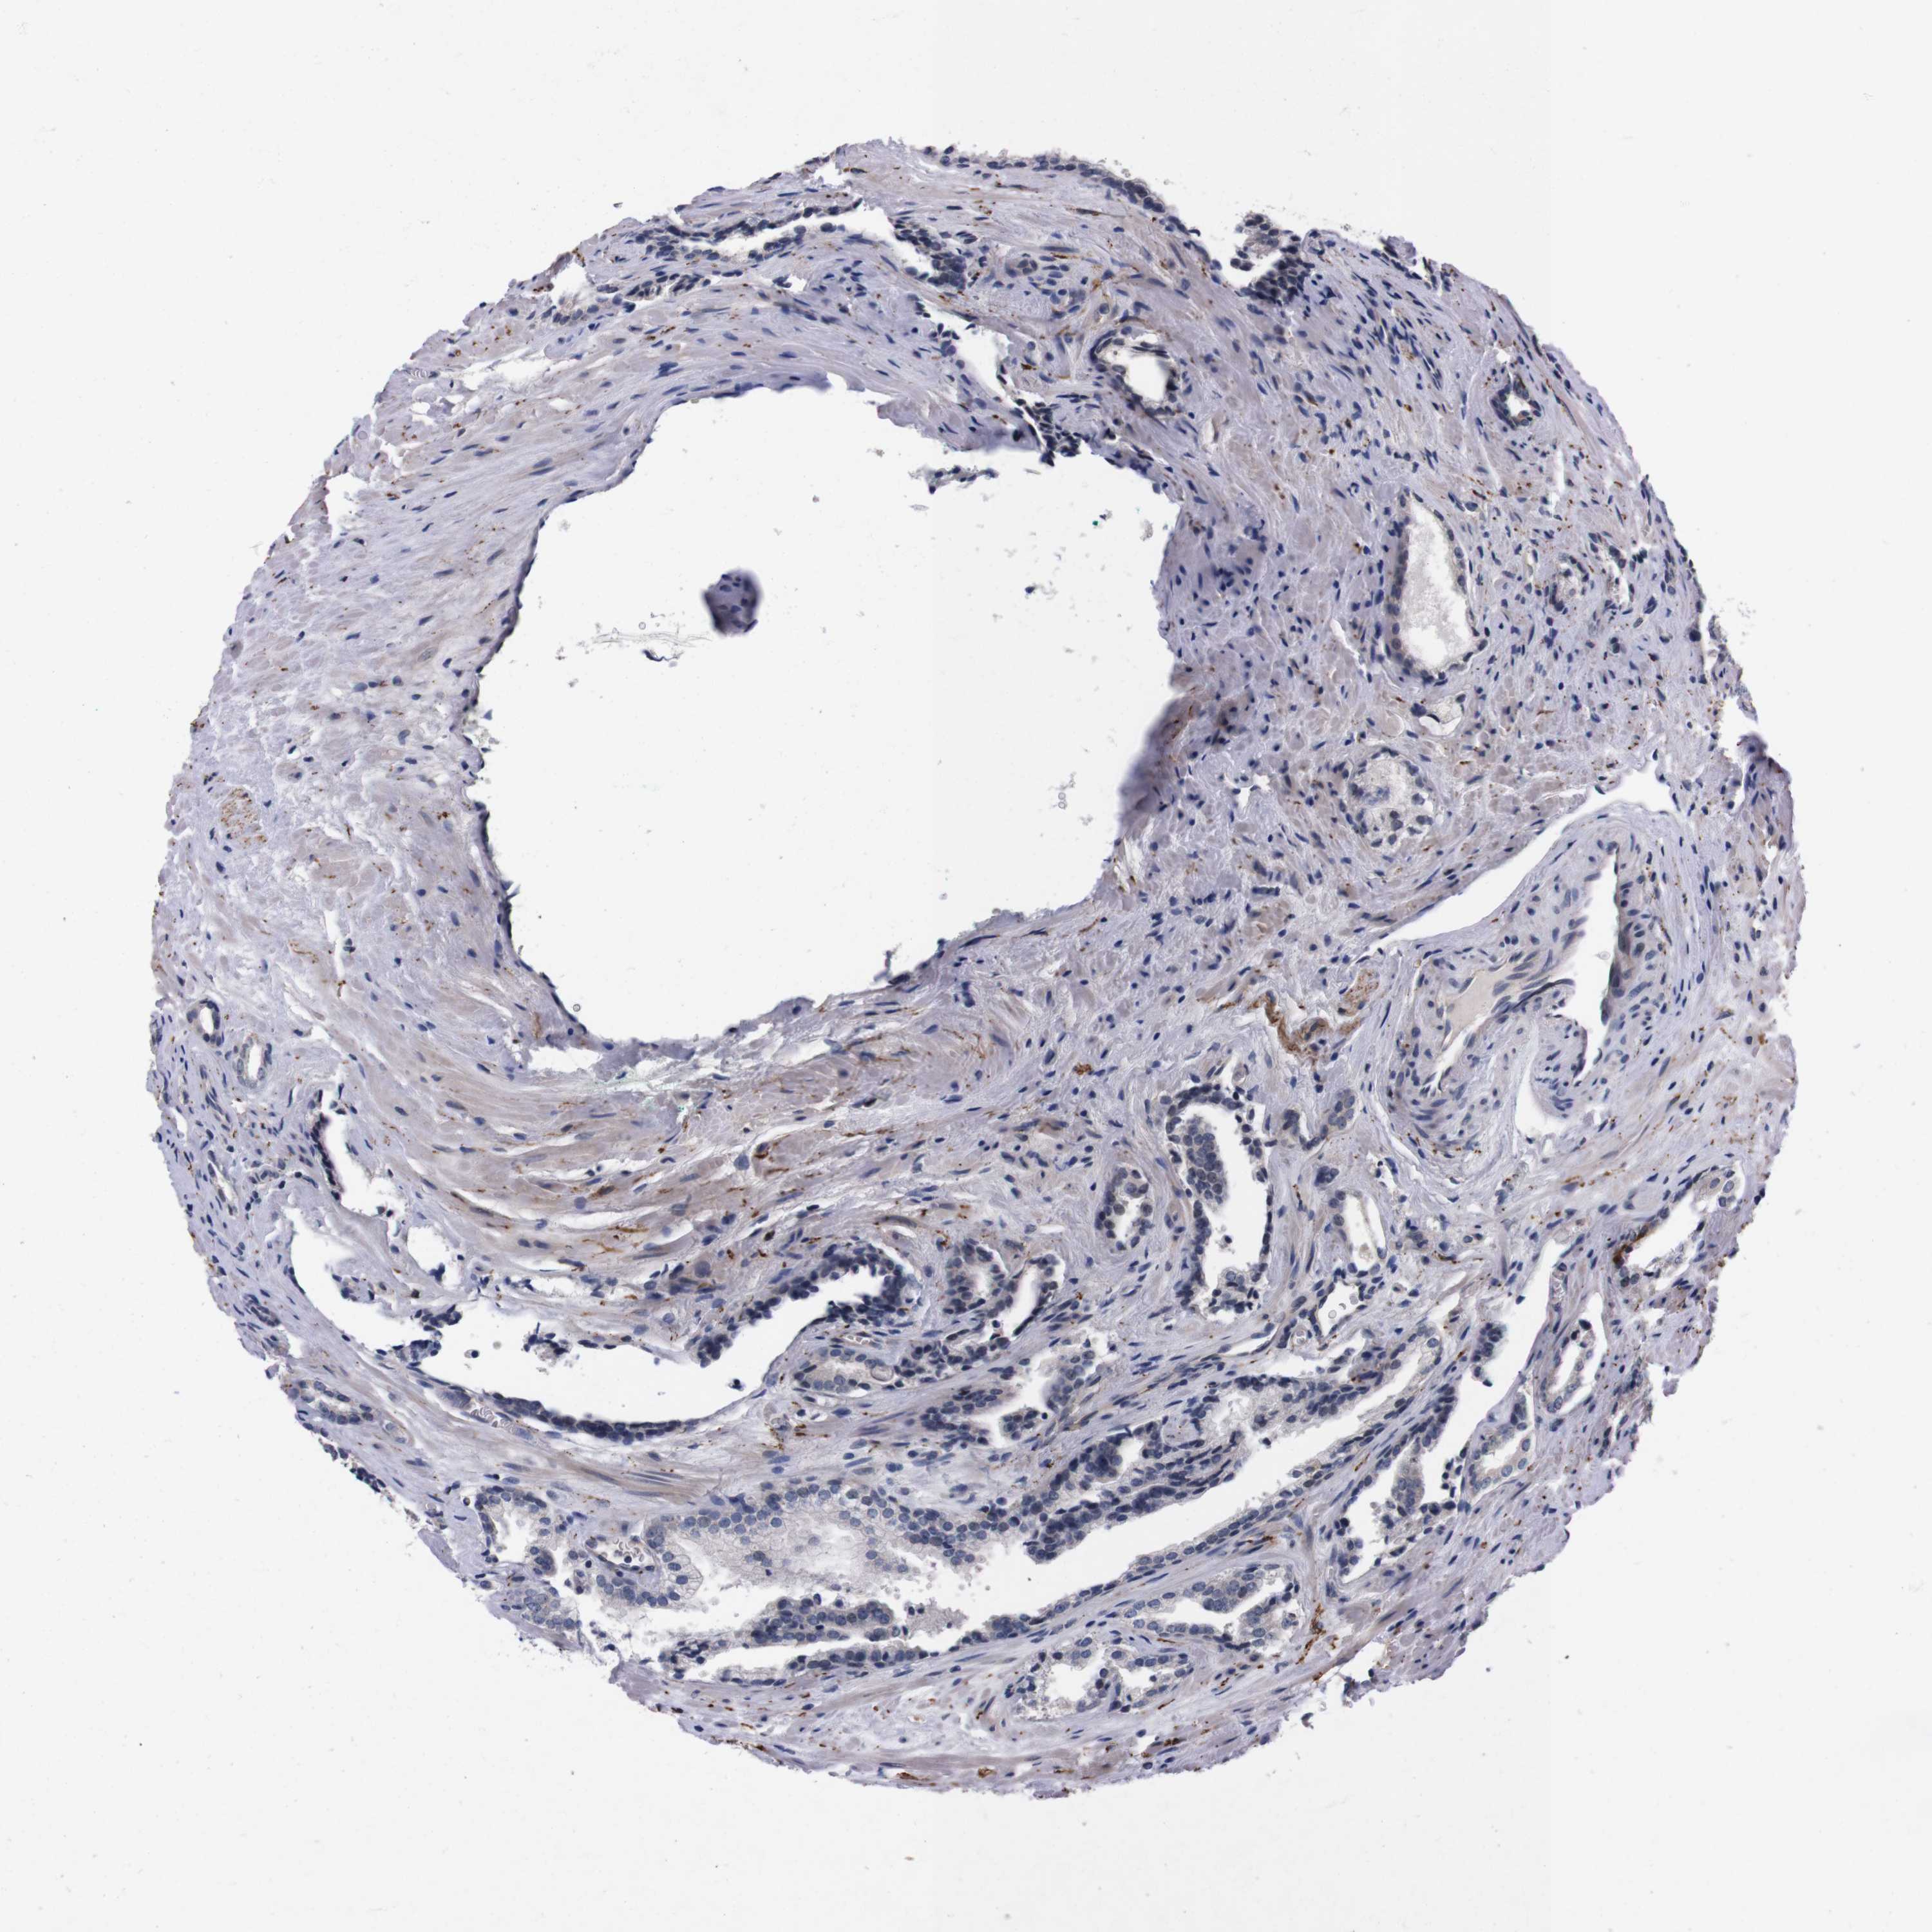

PROSTATE CANCER - Protein expressioni

A mouse-over function shows sample information and annotation data. Click on an image to view it in a full screen mode. Samples can be filtered based on level of antibody staining by selecting one or several of the following categories: high, medium, low and not detected. The assay and annotation is described here.

Note that samples used for immunohistochemistry by the Human Protein Atlas do not correspond to samples in the TCGA dataset.

Antibody stainingi

Antibody staining in the annotated cell types in the current human tissue is reported as not detected, low, medium, or high, based on conventional immunohistochemistry profiling in selected tissues. This score is based on the combination of the staining intensity and fraction of stained cells.

Each image is clickable and will lead to virtual microscopy that enables deeper exploration of all samples and also displays staining intensity scores, fraction scores and subcellular localization as well as patient and tissue information for each sample.

Antibody HPA006746

Antibody CAB009805

Staining

High

Medium

Low

Not detected

Intensity

Strong

Moderate

Weak

Negative

Quantity

>75%

75%-25%

<25%

None

Location

Nuclear

Cytoplasmic/membranous

Cytoplasmic/membranous,nuclear

Adenocarcinoma, Low grade

Adenocarcinoma, High grade